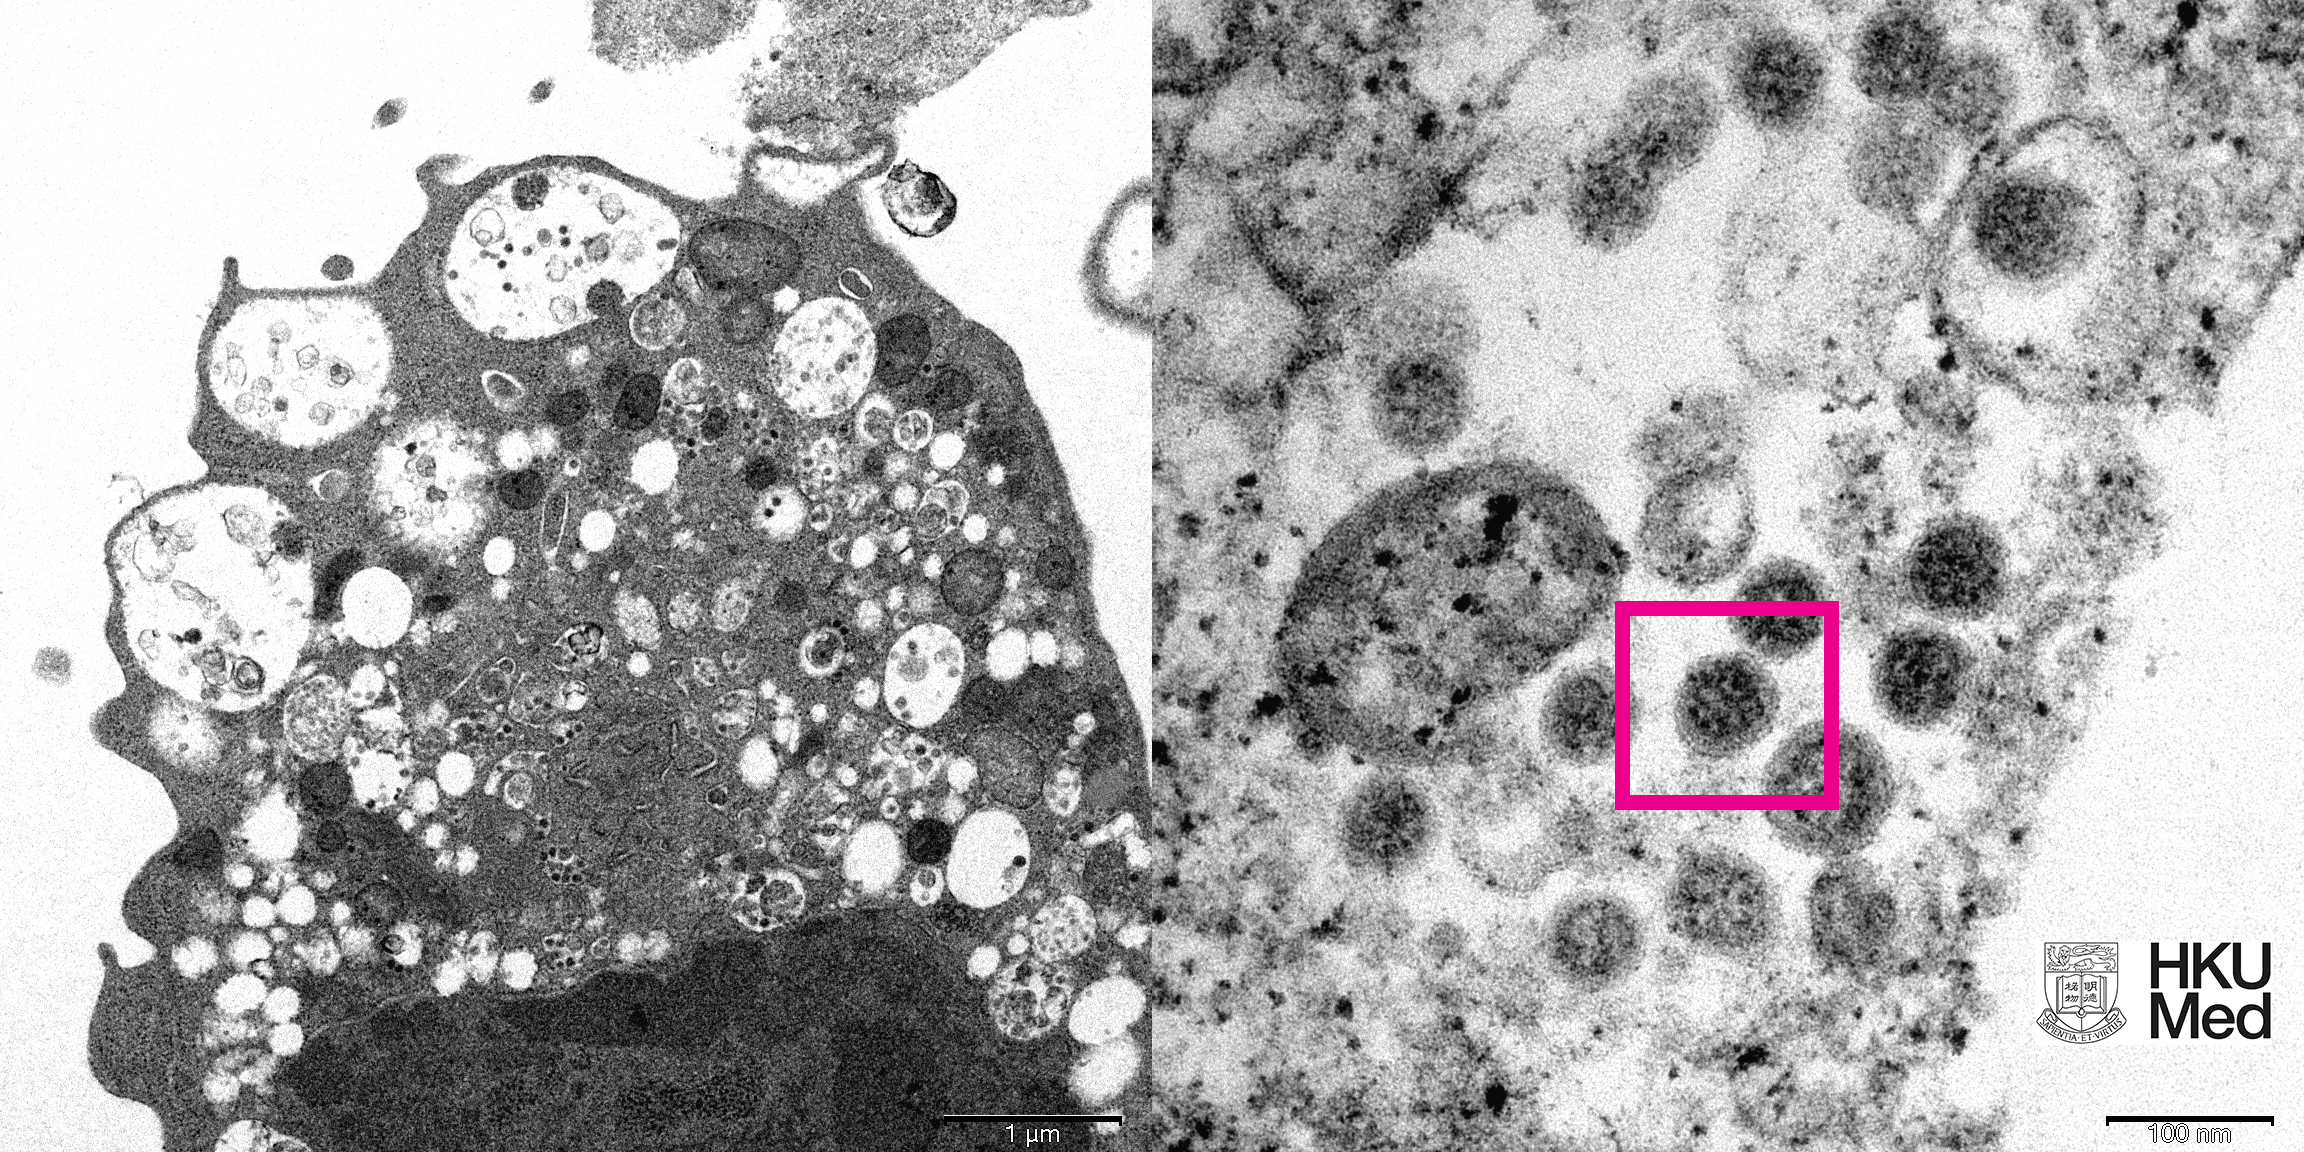

《澎湃新闻》报导,根据港大公布的照片显示,图左照片为低倍电子显微镜下感染新型冠状病毒奥密克戎(Omicron)变异株后的猴肾细胞(Vero E6)。照片显示细胞受损,肿胀囊泡,囊泡内含有黑色小病毒颗粒。显示细胞受损,肿胀囊泡,囊泡内含有黑色小病毒颗粒。

图右照片则为高倍电子显微镜下受感染的Vero E6细胞。照片显示病毒颗粒表面呈现皇冠形的刺突蛋白(红框处)。

港大医学院发布的低倍电子显微镜下感染新型冠状病毒奥密克戎变异株后的猴肾细胞(Vero E6)照片显示,细胞受损,肿胀囊泡,囊泡内含有黑色小病毒颗粒。

同时,高倍电子显微镜下受感染的Vero E6细胞照片显示,病毒颗粒表面呈现皇冠形的刺突蛋白。